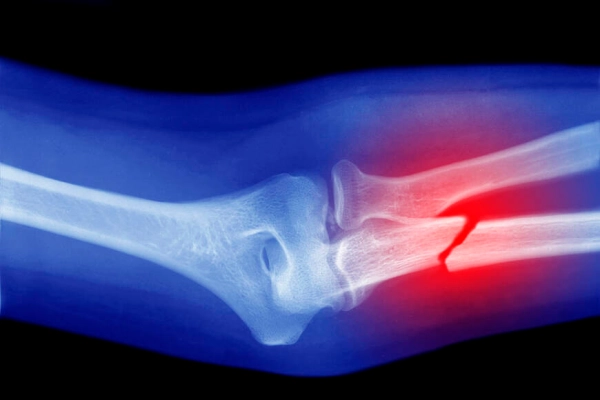

TEK ENJEKSİYONLA ÜÇ DAKİKADA SABİTLENİYORYeni tedavi, platin vidalarla yapılan cerrahi müdahalelerin yerine tek bir enjeksiyonla uygulanıyor. Yapıştırıcı, kırık kemik parçalarını sadece üç dakika gibi kısa bir sürede birleştirerek sabitliyor. İlk testler, bu yöntemin enfeksiyon riskinin de platin kullanımına kıyasla daha düşük olduğunu gösterdi.

İKİNCİ AMELİYAT İHTİYACINI ORTADAN KALDIRIYORYöntemin en büyük avantajlarından biri, ikinci bir ameliyat ihtiyacını ortadan kaldırması. Geleneksel tedavilerde plaka ve vidaların çıkarılması için genellikle bir yıl sonra ikinci bir operasyon gerekirken, "Bone-02" yapıştırıcısı iyileşme sürecinde kemikle bütünleşiyor ve zamanla vücut tarafından doğal olarak emiliyor. Cho Sun Daily'nin aktardığı bir vakada, bileği kırılan bir hastanın yalnızca 3 santimetrelik bir kesiden yapılan enjeksiyonla üç dakikada tedavi edildiği ve üç ay sonraki kontrollerde kırığın tamamen iyileştiği gözlemlendi.